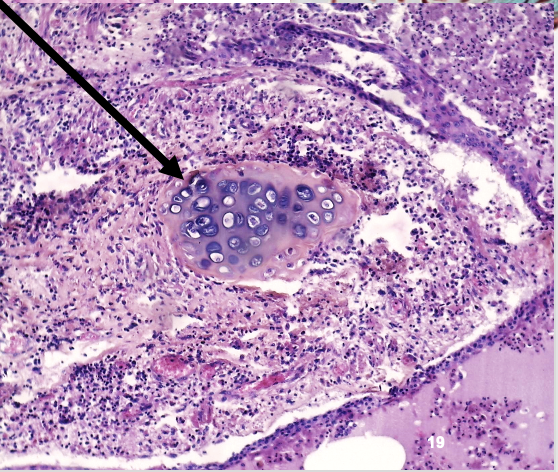

Jichtophus: pathologische veranderingen

onder dermis:opstapeling van uraat kristallen (=fijne witte naalden en amorfe hematoxifiele structuren )

inflammatoire reactie: lymfocyten, macrofagen & reuscellen

welk preparaat

jichtophus

jichtophus: wat zie je op deze uitvergroting

stapeling van uraatkristallen onder de dermis